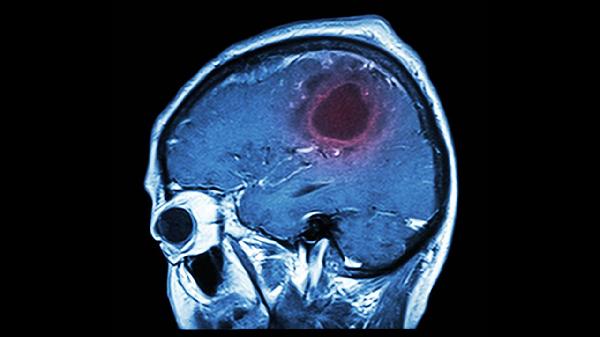

精神分裂症患者常出现脑室扩大、灰质体积减少,尤其是前额叶皮层和海马区。影像学检查可观察到颞叶、顶叶皮质变薄,这些区域与认知功能和情绪调节密切相关。部分患者丘脑体积缩小,可能导致感觉信息过滤功能受损。